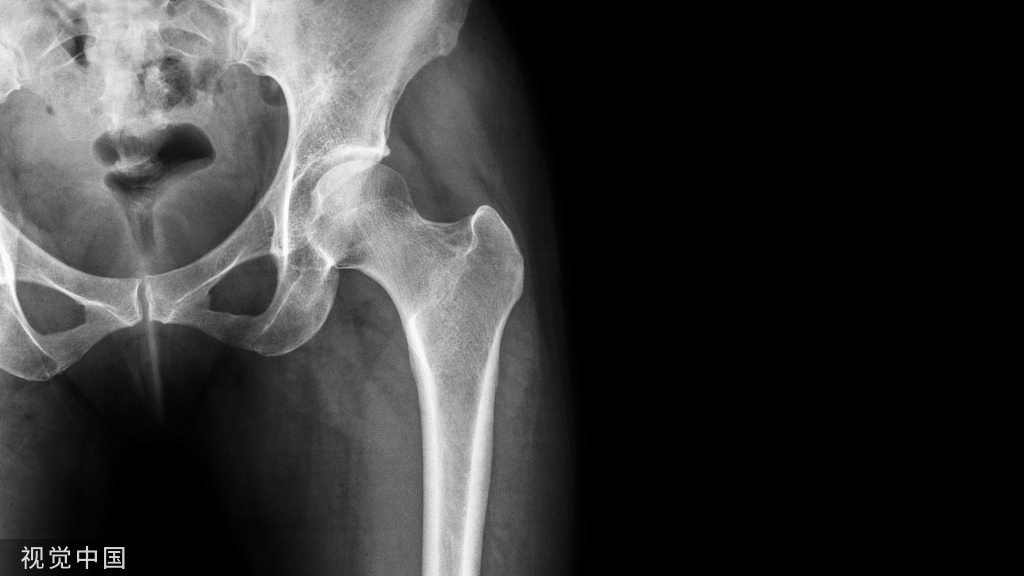

由Vidal J于1973年首次报道。骶髂螺钉是骶骨骨折及骨盆后环不稳使用最多的内固定方式之一,总体适用于无移位或移位较少的骶髂关节损伤、骶骨骨折。手术可在局麻下,经皮微创进行。

由Vidal J于1973年首次报道。骶髂螺钉是骶骨骨折及骨盆后环不稳使用最多的内固定方式之一,总体适用于无移位或移位较少的骶髂关节损伤、骶骨骨折(Mendel T, 2011)。手术可在局麻下,经皮微创进行。